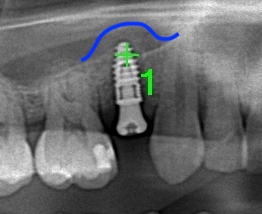

レントゲン画像です。青線部分が上顎洞が挙上された

部分です。

このように副鼻腔を持ち上げてインプラントを埋入する方法を

ソケットリフトと言います。しかしソケットリフトで持ち上げる量は

およそ3mmが限界でそれ以上になりましたらサイナスリフトという

方法になります。